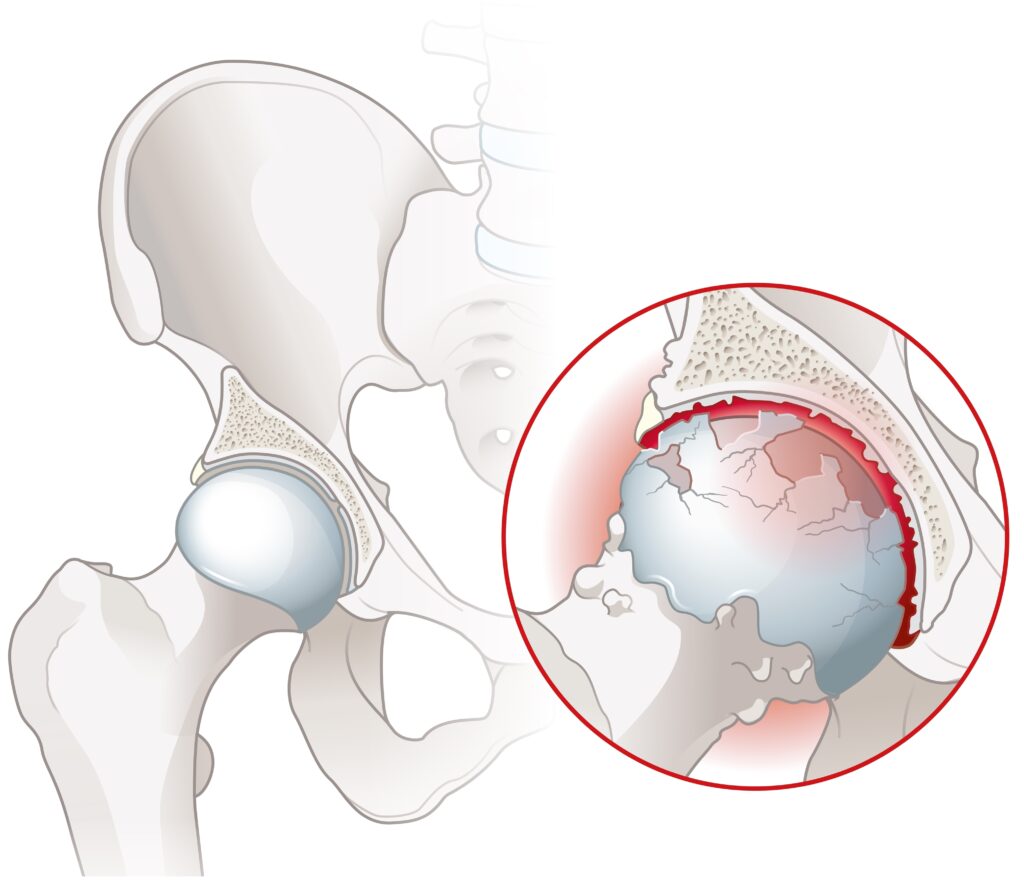

- Coxartroză avansată (uzură severă a cartilajului articular).

- Necroză avasculară a capului femural.

Coxartroza